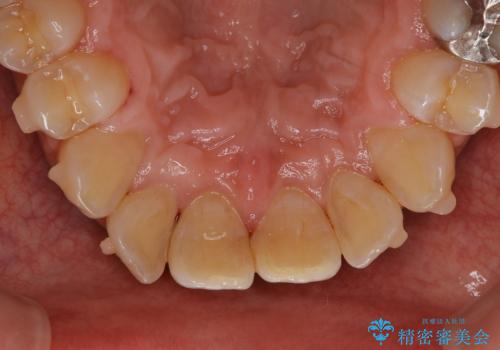

しぶといステインもエアフローワンで1日でキレイに!!

- インビザラインの治療中ですが、歯石やステインが気になるとのことでした。

コーヒーが大好きでよく飲むそうです。

全体的に歯石やステインが付着していたため、エアフロー60分コースを行いました。